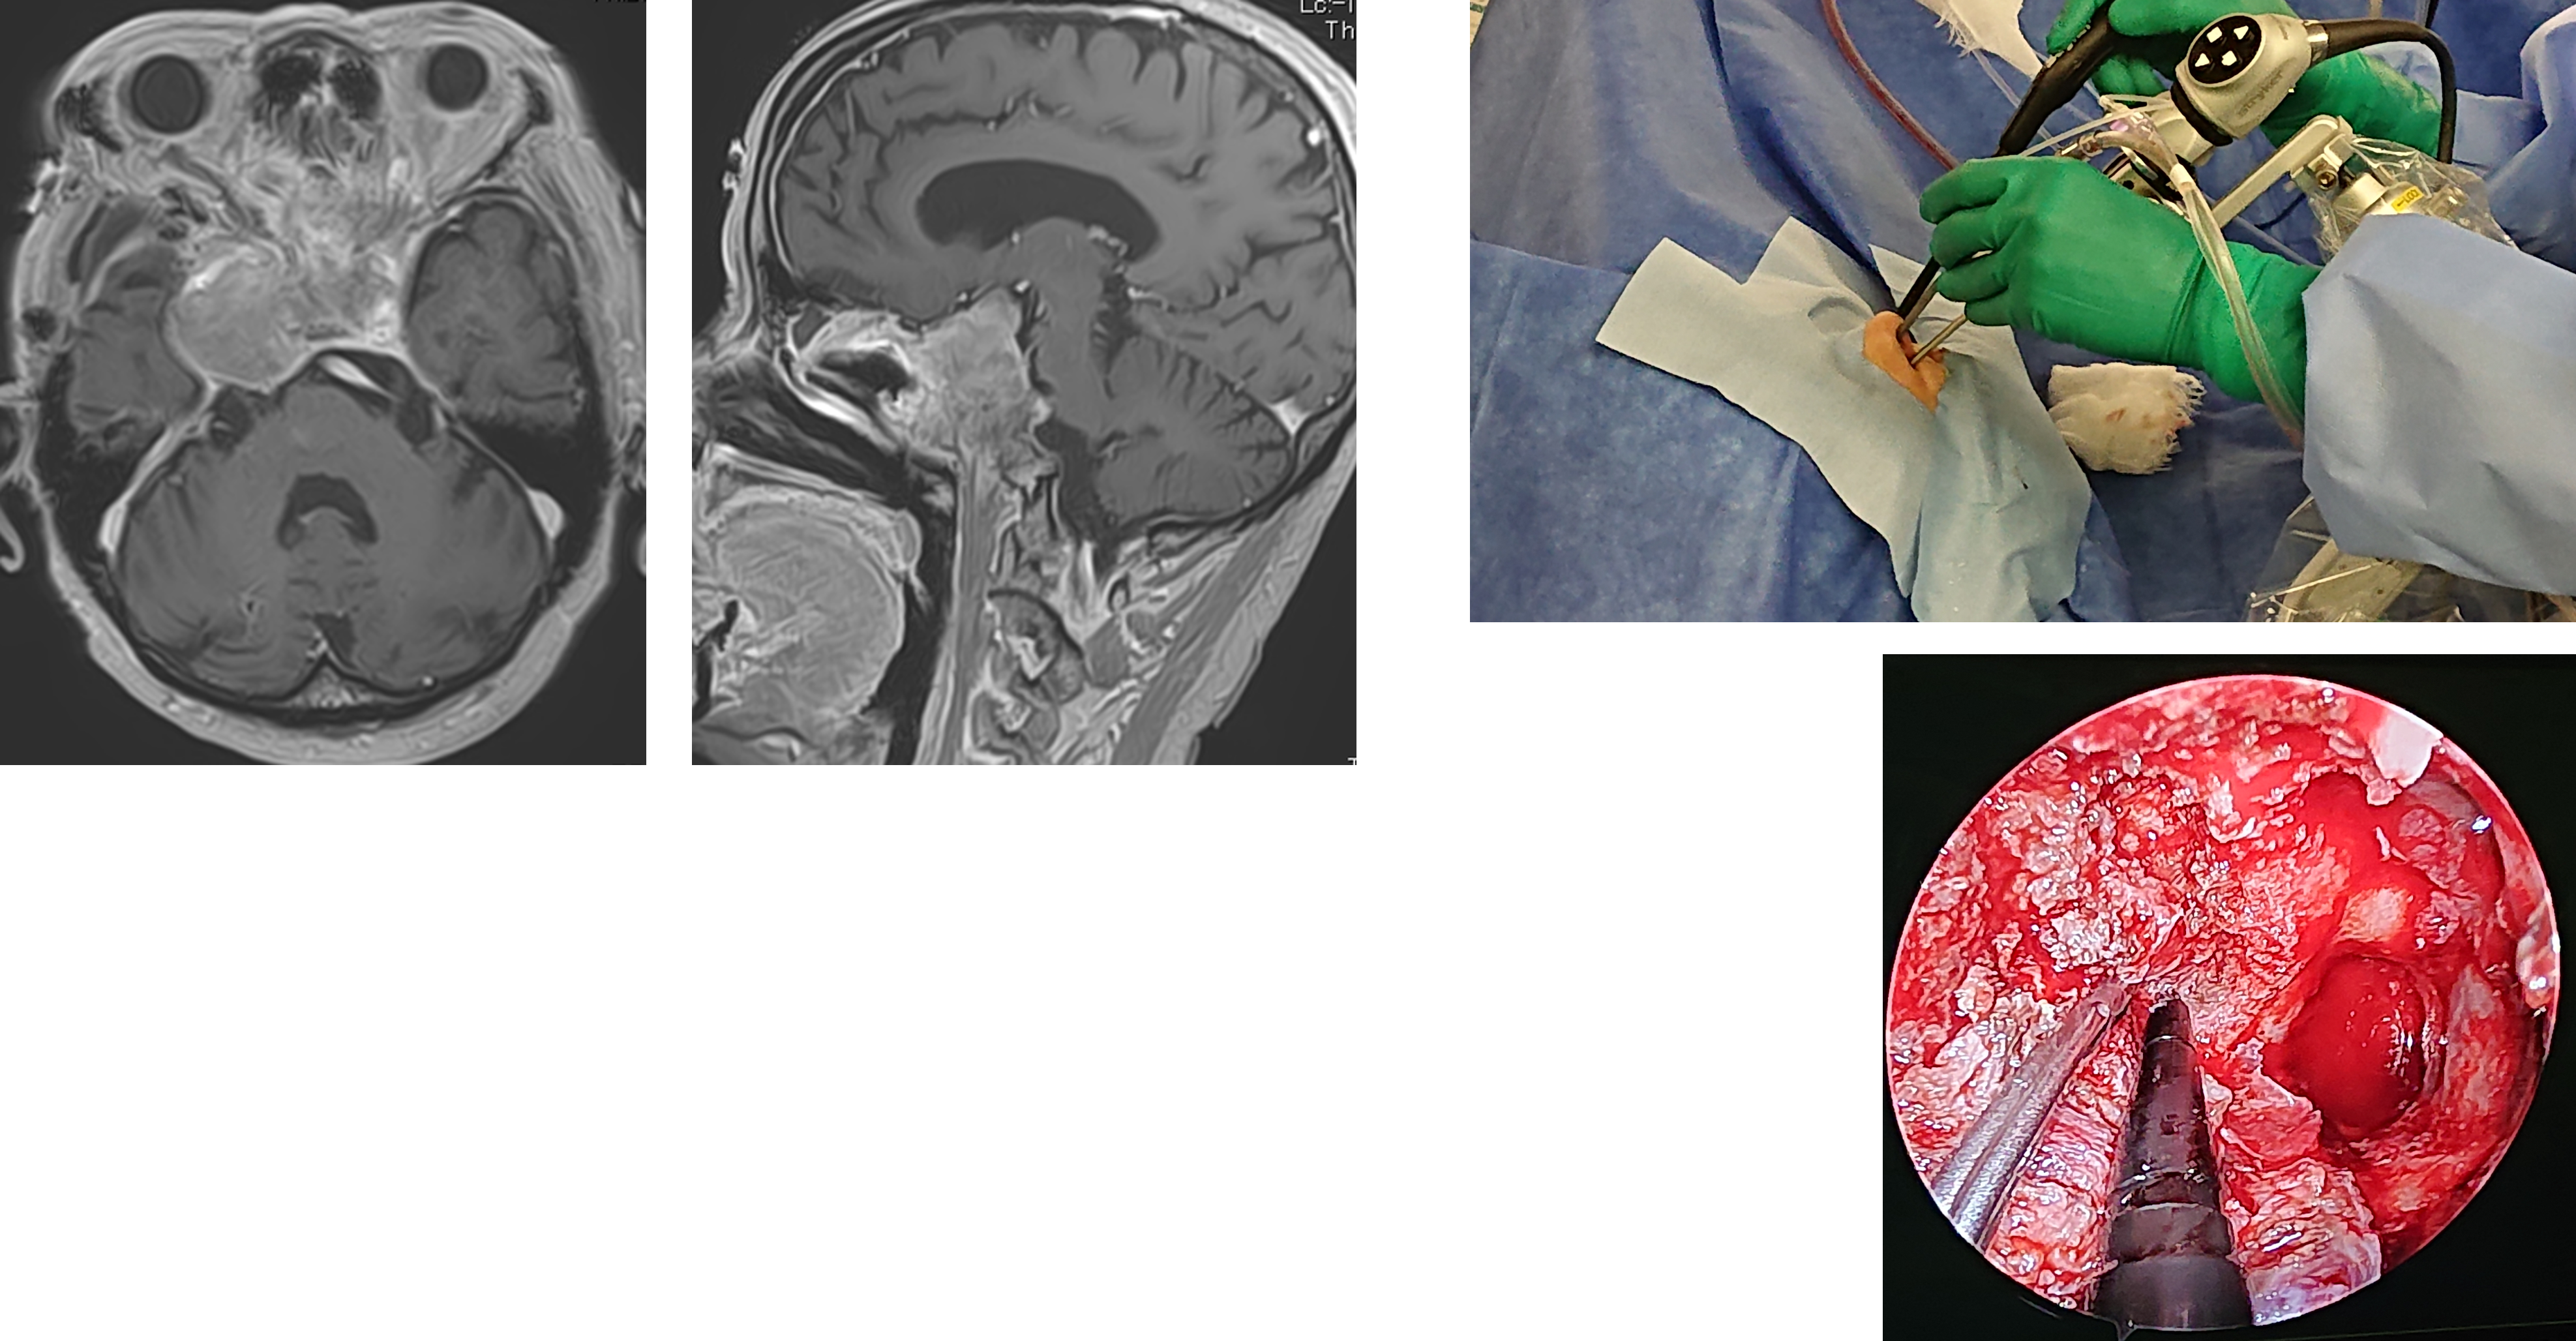

顕微鏡&外視鏡システム&内視鏡システムを用いた低侵襲治療

脳神経外科手術は手術用顕微鏡が導入されたことで飛躍的な進歩を遂げ、微細な手術を行うことが可能となりました。一方で、手術用顕微鏡は、焦点深度が浅い、器械自体が大きくスペースをとる、術者の姿勢が限られ疲労感が強くなるなどの問題点を抱えております。

当院は最新の顕微鏡、外視鏡システム、内視鏡システムを導入しています。

外視鏡手術の特徴の一つとして、術者の姿勢を変えずにカメラの位置を自由に変えることができ、患者さんの術中体位に無理が少なくなり、術後の体の痛みが減少します。また、内視鏡を使用することで、皮膚切開や開頭範囲も小さくすることができ、低侵襲な治療が行えます。また、顕微鏡や外資橋では見えない死角を確認することができ、安全かつ最大限の摘出を行うのに大変有用なツールです。

術中蛍光診断

通常の手術用顕微鏡で観察するだけでは、腫瘍と正常脳との境界が分かりづらいことが多々ありますが、特に運動、言語などに関係する脳の近くでは、正常脳を傷つけずに腫瘍を最大限の摘出することが重要です。手術中に5-アミノレブリン酸(5-ALA)という蛍光プローブを用いると、特殊な光のもとで腫瘍が赤色に染まるため、より正確に腫瘍摘出を行うことができます。